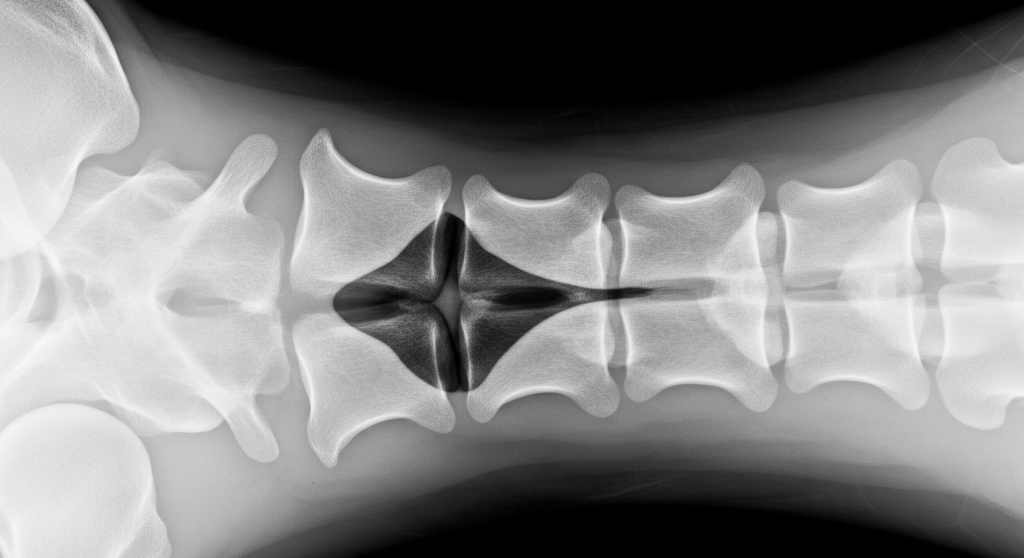

The Role of MRI in Diagnosing Disc Herniation

Magnetic Resonance Imaging (MRI) is the gold standard for diagnosing a disc herniation. The scan provides a clear, detailed picture of the spinal discs, revealing whether a tear has occurred and if the inner disc material is pressing on a nerve root or the spinal cord. An MRI can distinguish between a simple disc bulge (where the disc pushes out slightly without a tear) and a true herniation. It can also identify other related issues, such as спинальный стеноз (narrowing of the spinal canal) or nerve compression. The precise information from an MRI is crucial for determining the most effective treatment plan, which may range from physical therapy to surgical intervention.